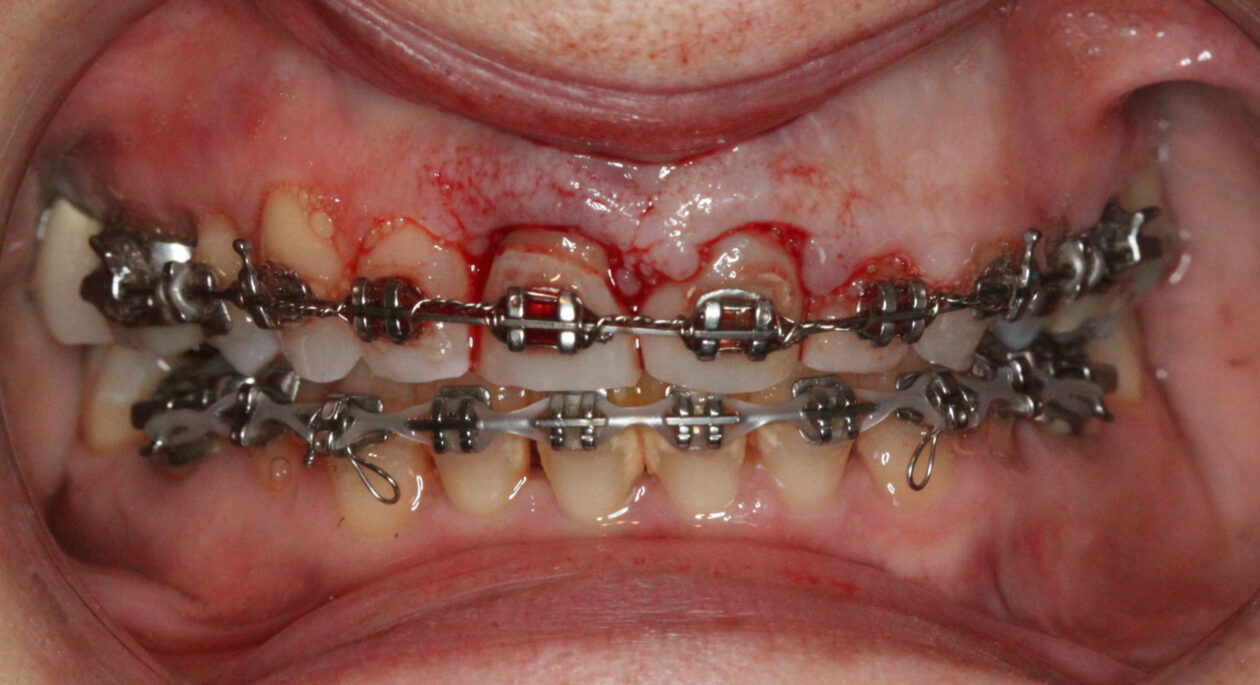

Extraction after forced eruption can allow for a much more favorable implant site compared with extraction alone. This is possible because the tension applied to the periodontal ligament during orthodontic tooth movement stimulates osteoblastic activity to induce new bone formation. As the tooth moves coronally during extrusion, soft tissue and bone attached to the periodontal fibers migrate in the same direction. As a result, forced eruption can be used to enhance the quality and quantity of both hard and soft tissue of future implant sites.

The special report presented below illustrates how orthodontic extrusion was successfully used to improve the periodontal architecture prior to the placement of two adjacent implants in the esthetic zone and thus allowed for a more ideal restorative result.